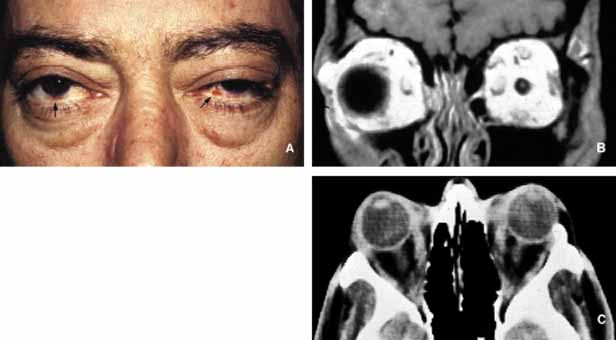

Another type of orbital tumor that originates from blood vessels is hemangiopericytoma, which is a pseudoencapsulated spindle cell tumor composed of vascular pericytes183 (Fig. 17). In these tumors the reticulin network surround the individual tumor cells in hemangiopericytoma as opposed to small groups of epithelial cells in capillary hemangioma. In hemangiopericytoma the tumor cells stain positively with factor VIII, CD34, and occasionally vimentin. The histopathologic pattern that may present considerable pleomorphism with increased number of mitotic figures may vary from one zone to the other. The degree of pleomorphism and high number of mitotic figures are not clear cut indications of malignancy; as a matter of fact, the biological behavior of this tumor cannot be determined based on its histopathologic appearance. Metastatases after many years have been described.184 The best treatment for hemangiopericytoma is surgical excision.

Fig. 17 Hemangiopericytoma. Axial T1-weighted MRI showing a well-encapsulated large mass located in the medial orbit with compression onto the globe and the optic nerve (A). The signal intensity varies within the mass because of its vascular nature. Frame B depicts the well-encapsulated hemangiopericytoma at the time of its removal. Microscopic appearance reveals a mixture of haphazardly arranged spindle-shaped tumor cells with round and oval nuclei and scanty cytoplasms, mixed with a network of sinusoidal spaces and/or abnormally developed blood vessels. Moderate degree of pleomorphism and occasional abnormal mitotic figures are seen in this section (C). Although these malignant histopathology indicators have been reported in tumors that later metastasize; as a rule the biologic behavior of hemangiopericytoma cannot be dependably assessed based on its histopathology. Frame D shows the immunohistochemical staining with vimentin.